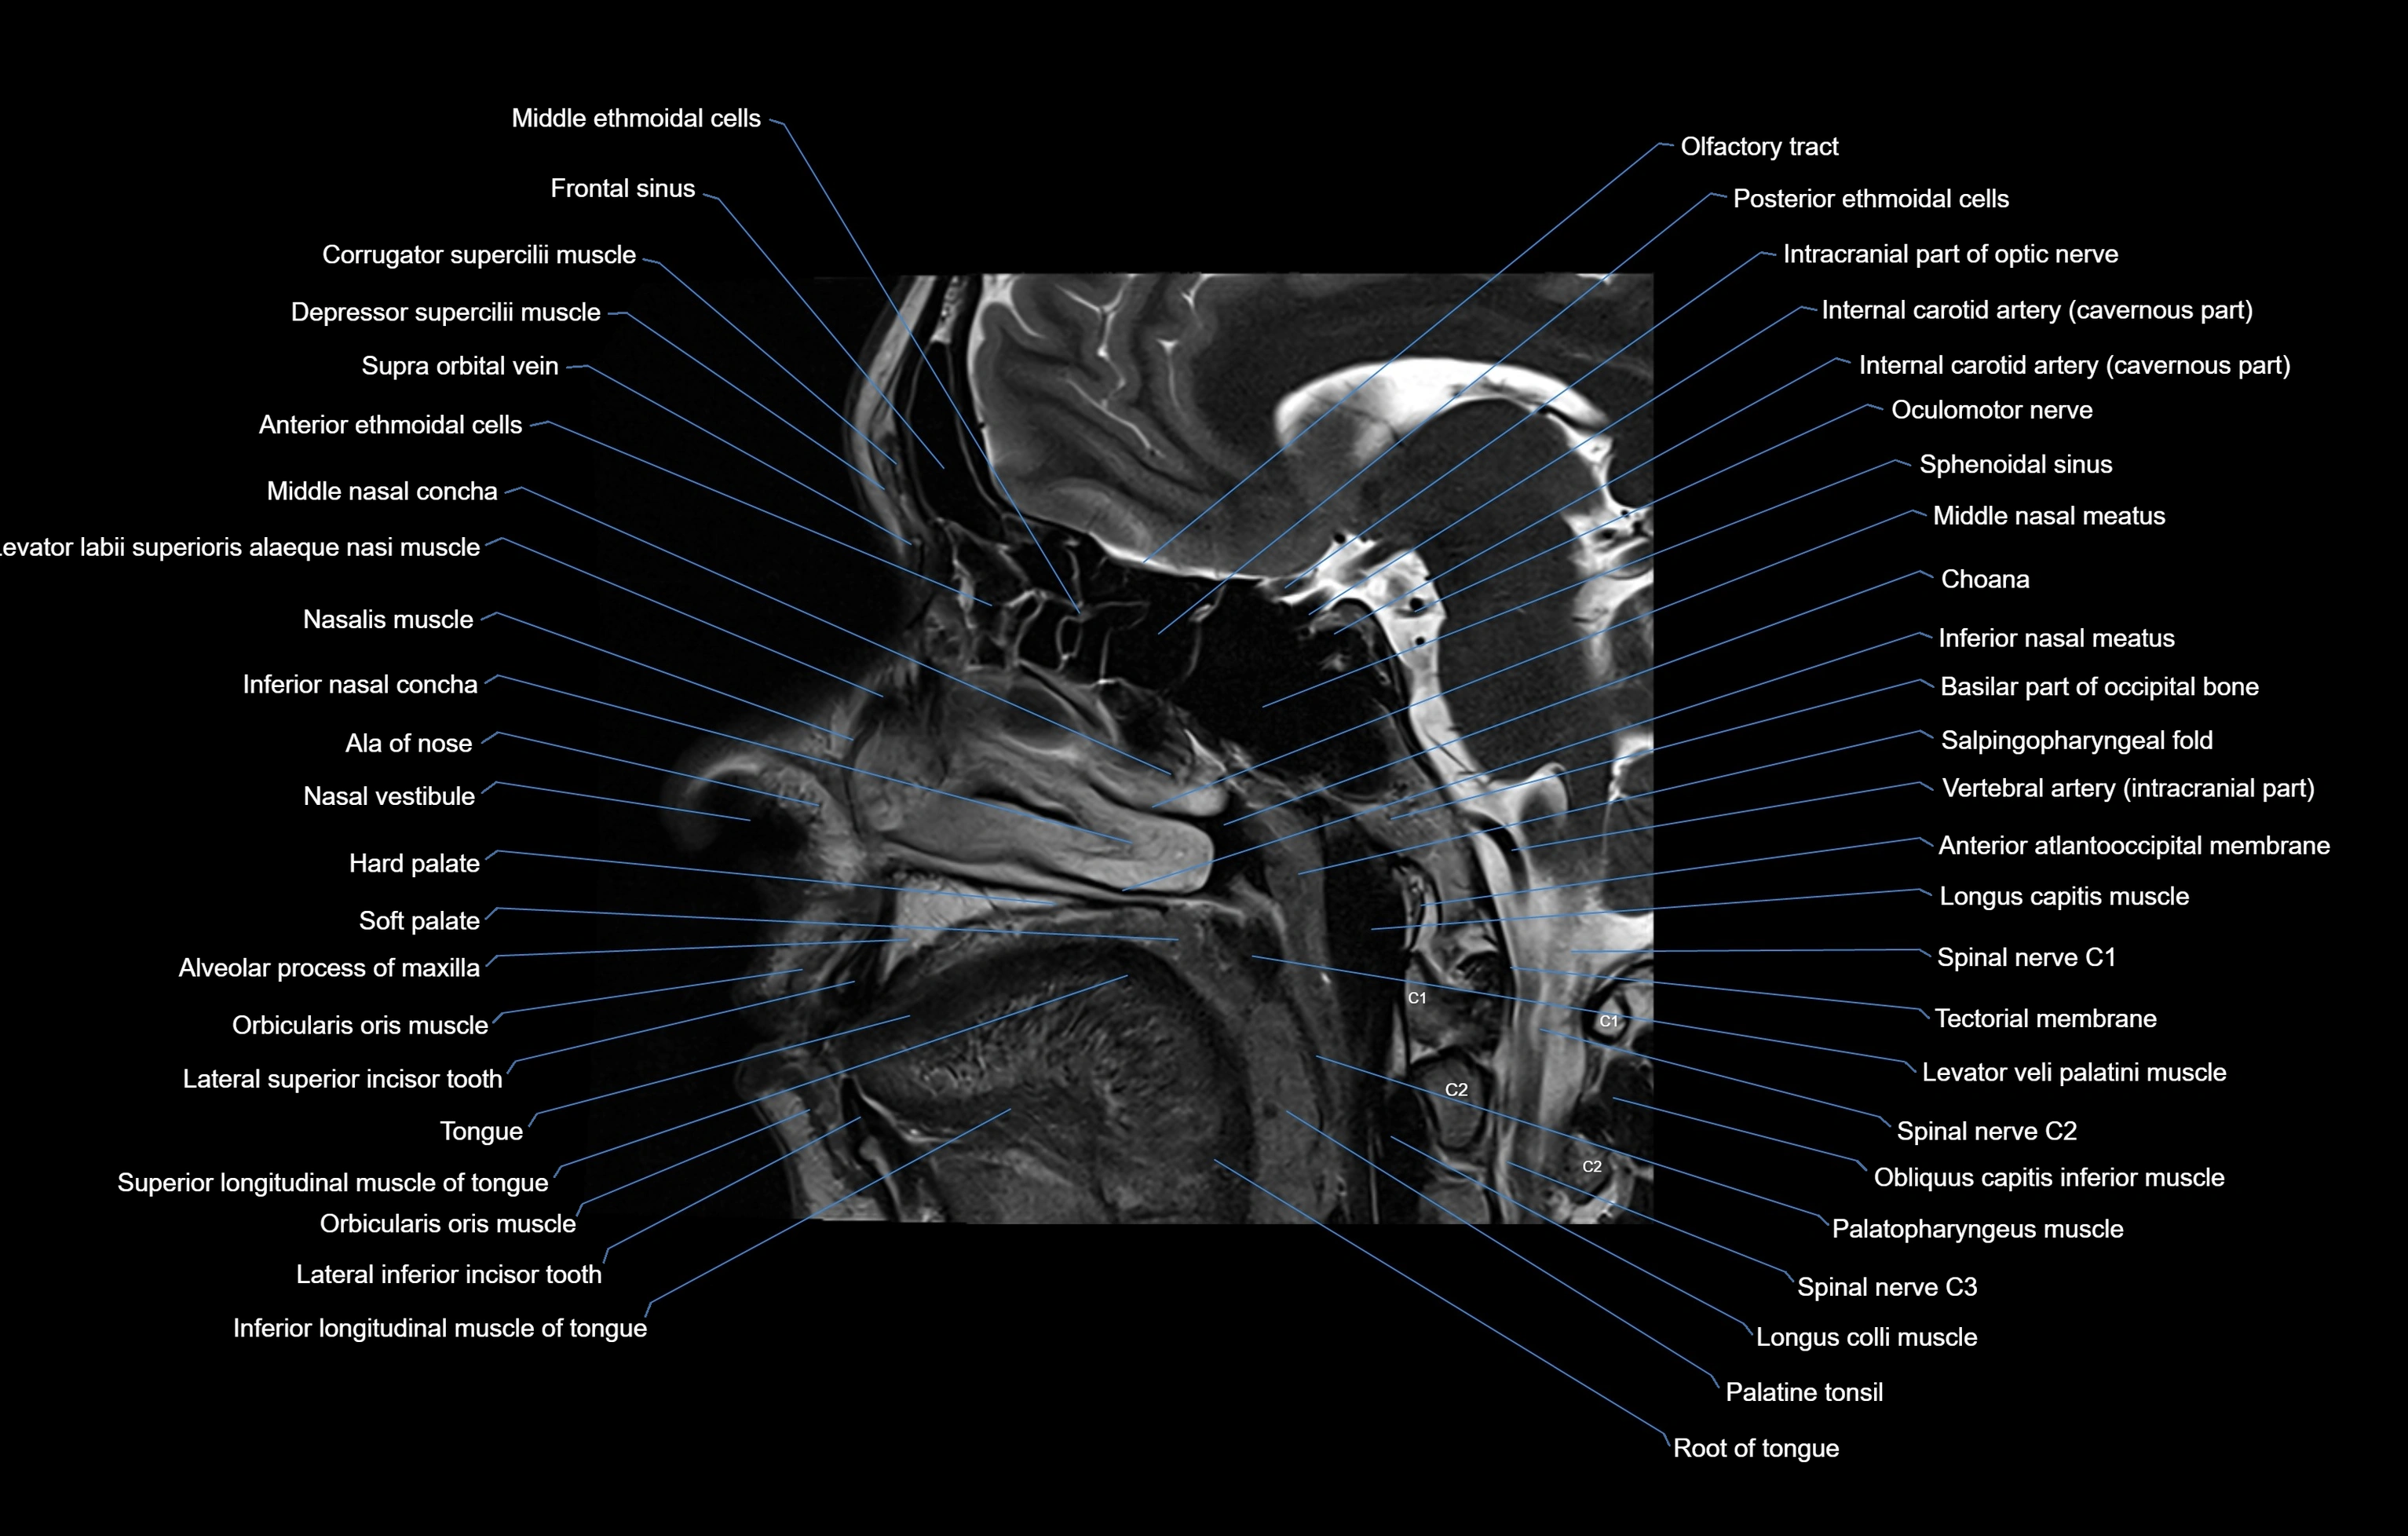

MRI images